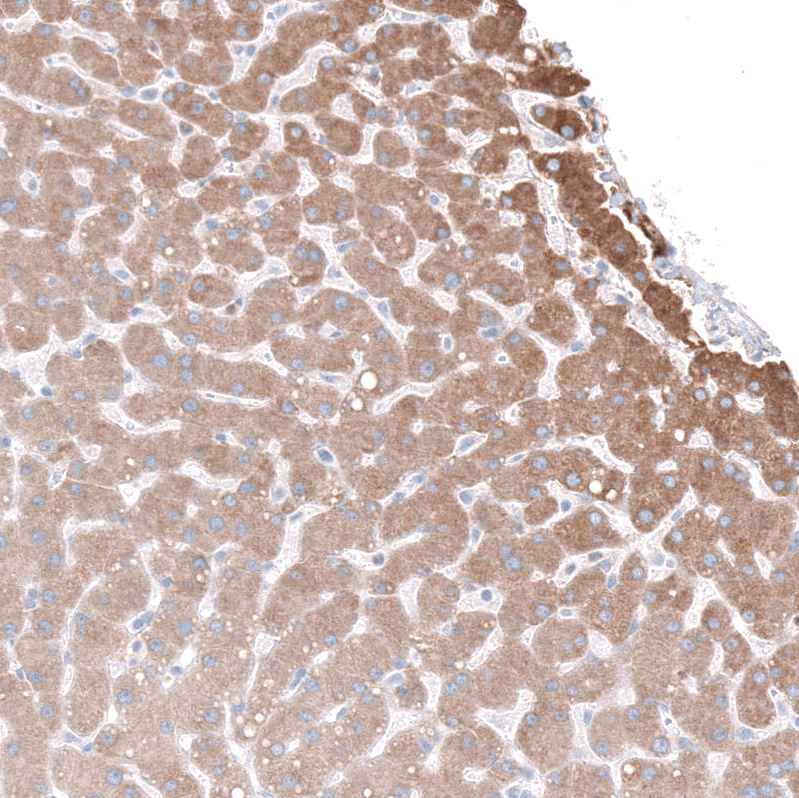

Immunohistochemistry analysis in human liver and skeletal muscle tissues using HPA016843 antibody. Corresponding INHBE RNA-seq data are presented for the same tissues.